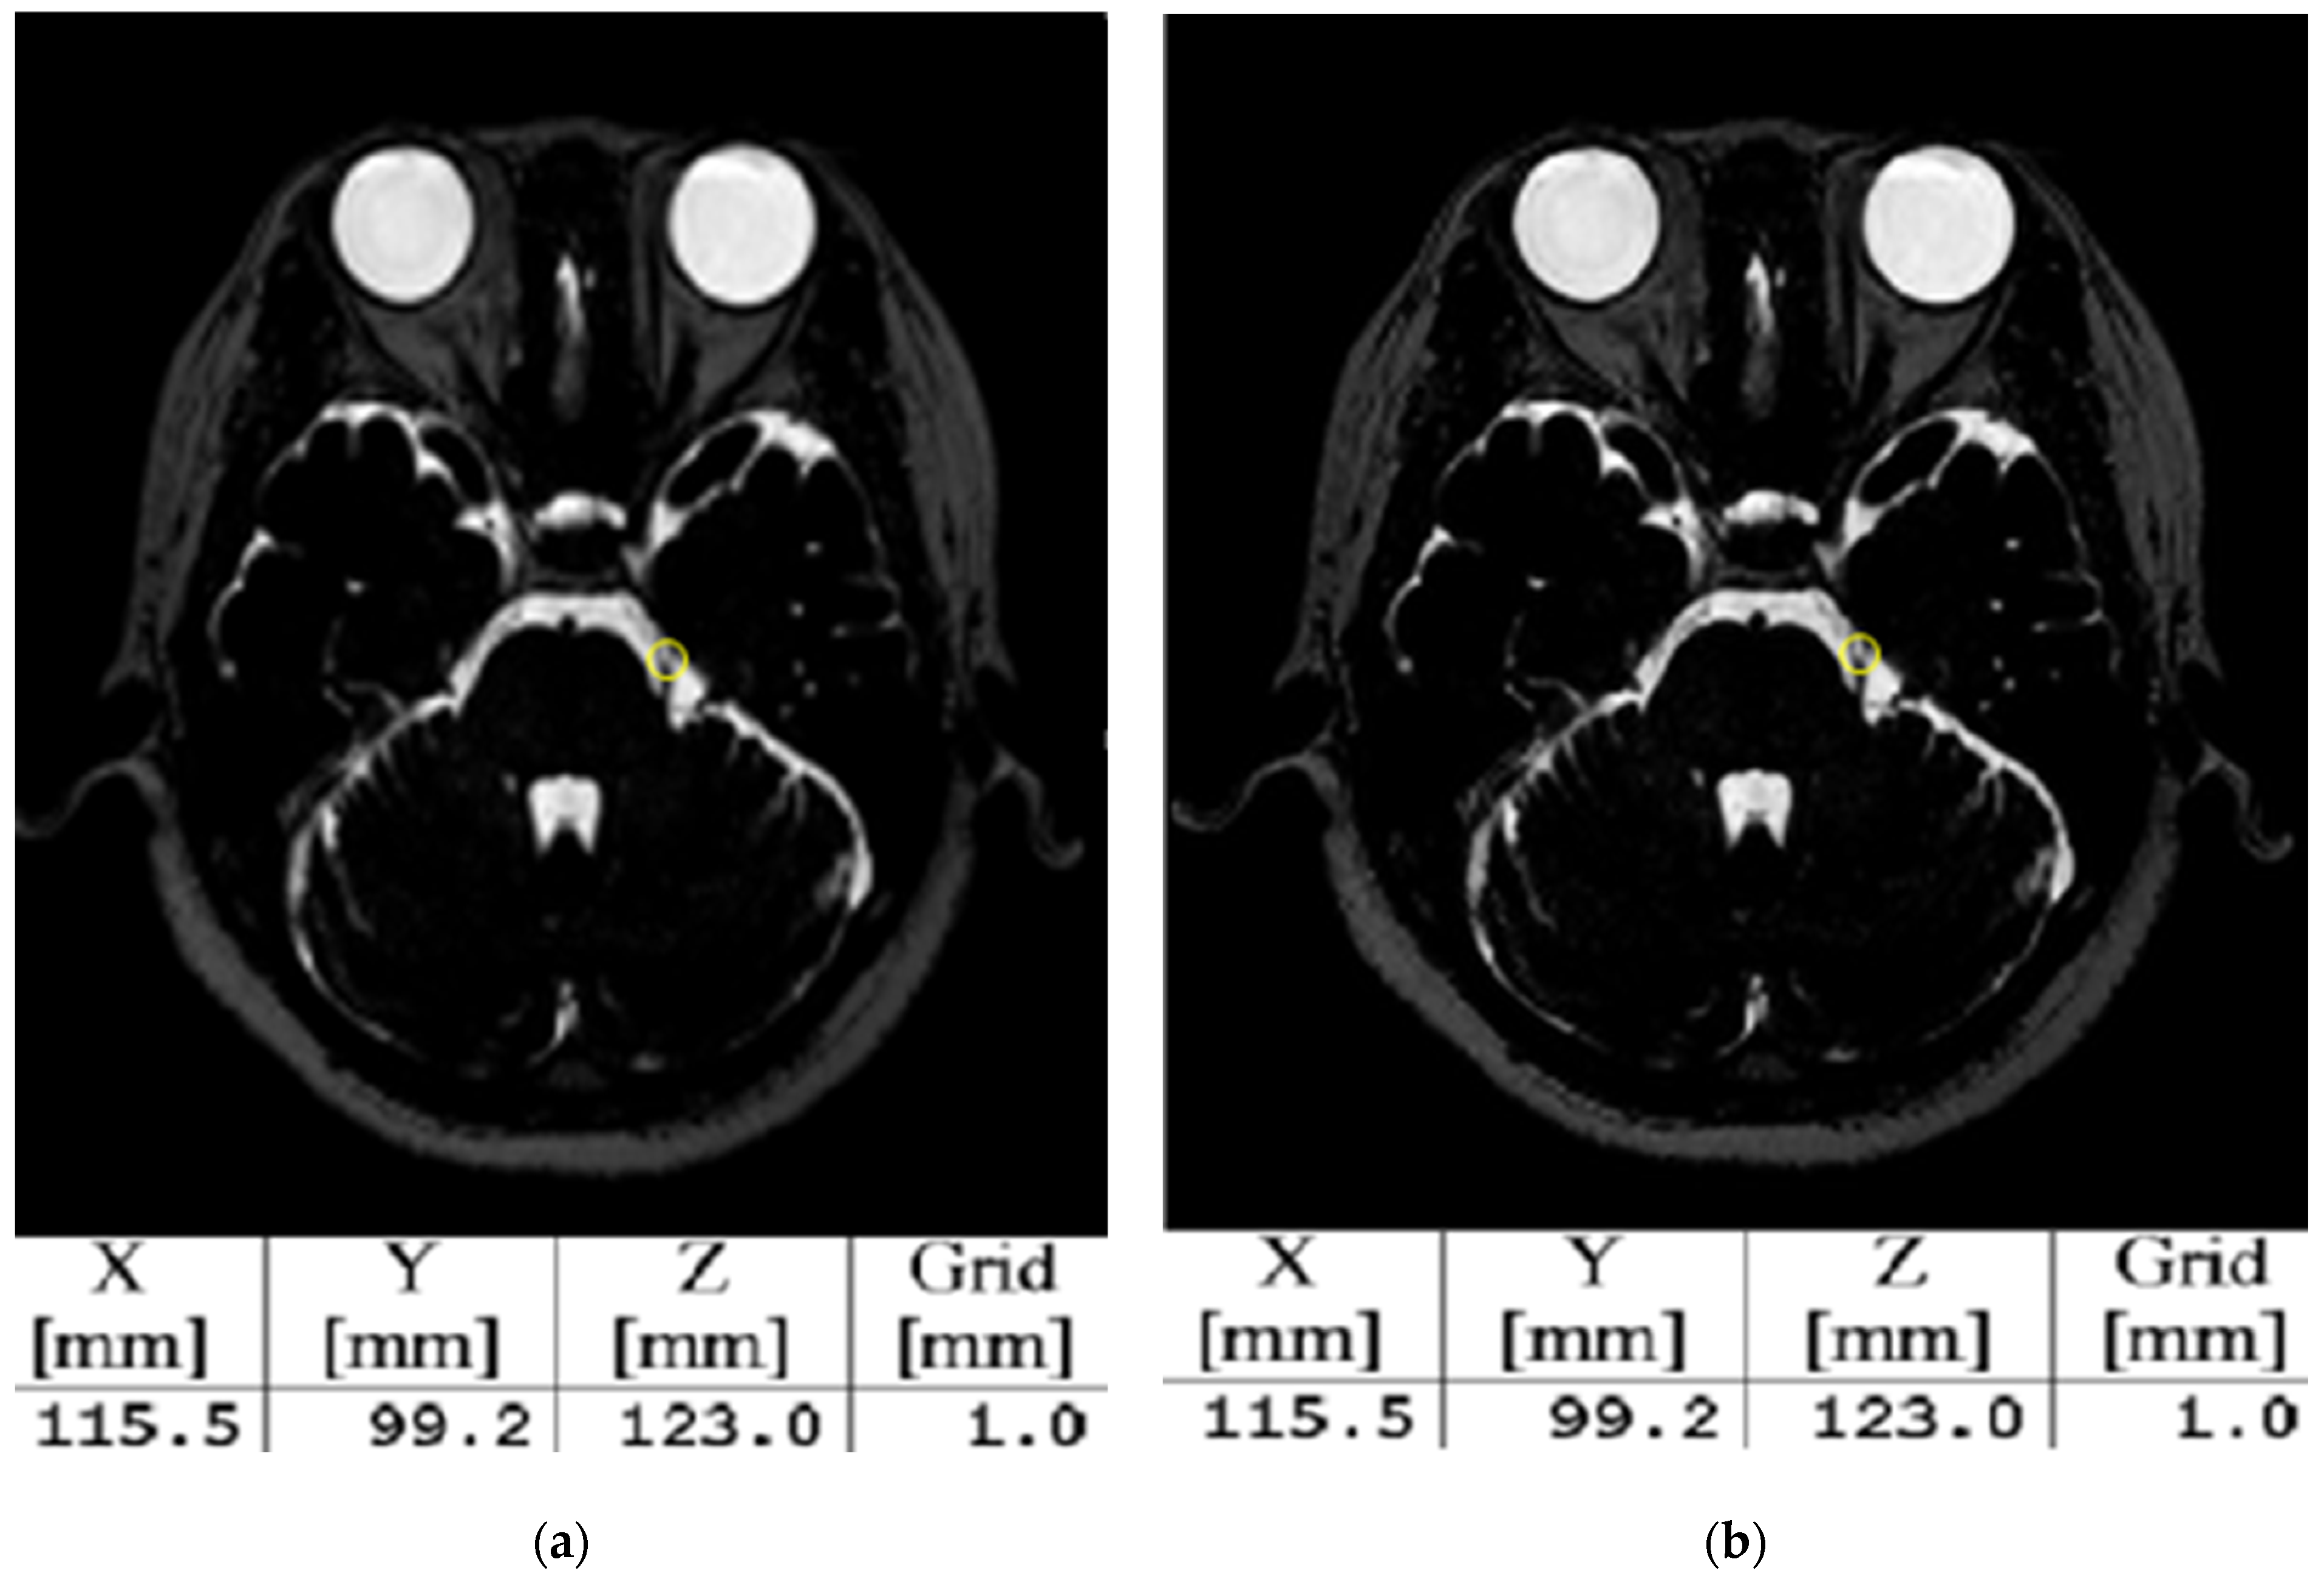

3.2. Evaluation of Image Quality and Coordinates of Surgical Planning